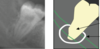

27

What radiographic sign is this showing in regards to M3M surgery risk to ID canal

Interruption of white lines / lamina dura of the ID canal